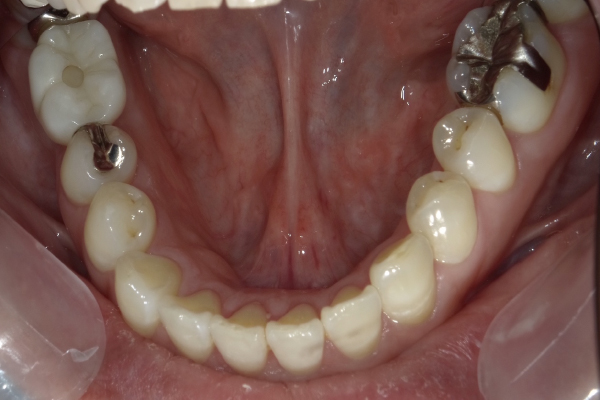

Case4

| 主訴 | 右側でもしっかり食事がしたい |

|---|---|

| 治療期間 | 約3か月 |

| 治療費 | 900,000円 |

| 治療内容 | 右下に2本のインプラントを入れ、上の被せ物は3本分入れました。お肉もなんでも食事ができるようになったと大変喜んでおられました。そう言ったお言葉をいただくと私も嬉しいです。 |

| 治療の リスク | インプラントも残っている歯と同様に歯周病になる可能性がある |